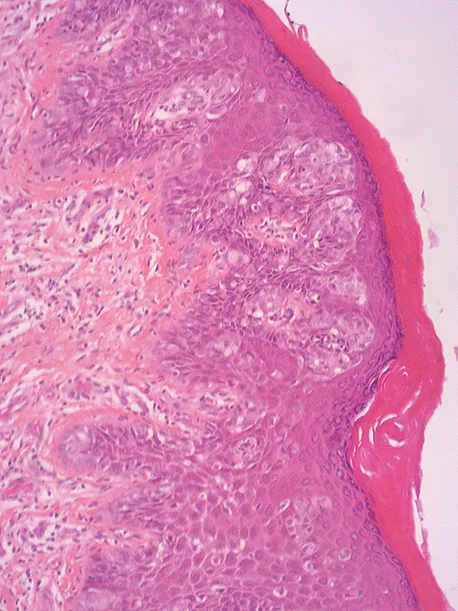

La maladie de Paget anale dans sa forme secondaire est un cas particulier clinico-histologique. Sa présentation clinique est polymorphe sous la forme de plaques érythémateuses planes, plus ou moins étendues, parfois suintantes, ulcérées, hypertrophiques et/ou lichénifiées par endroits, voire infiltrées, au niveau de la marge et de la peau péri-anale (Figure 4). Les diagnostics différentiels sont nombreux (Tableau 2) et des prélèvements à visée histologique sont indispensables au moindre doute, notamment en cas de « dermatose chronique » rebelle aux divers topiques. Sur le plan histologique, il s’agit d’un adénocarcinome intra-épithélial avec de multiples cellules arrondies, de grande taille, dotées d’un cytoplasme pâle abondant PAS+ et d’un noyau volumineux anisocaryotique (cellules de Paget) (Figure 5). C’est une affection rare, avec moins de 200 cas publiés dans la littérature. La localisation anale et péri-anale de la maladie de Paget correspondrait à moins de 20 % de ses formes extra-mammaires mais en représenterait la localisation la plus fréquente. Elle résulterait soit de l’extension de contiguïté d’un carcinome du canal anal ou de la vulve, soit de la propagation à l’anus d’un cancer viscéral synchrone ou métachrone distant, notamment colo-rectal, uro-génital ou mammaire. Elle survient surtout après l’âge de 50 ans (19, 20).

Figure n°5 : Aspect histologique d’une maladie de Paget